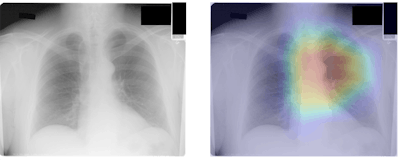

The researchers also noted that the algorithm generates gradient-weighted class-activation maps (Grad-CAM) to localize the anatomic regions that contributed to its age estimate.

These maps show that CXR-Age commonly focuses on the mediastinum, the cardiac silhouette, and the aortic knob -- anatomy that dilates and becomes tortuous with aging.

"Activations were also seen over other anatomy, including the diaphragmatic silhouette, the upper mediastinum, and the low neck," the authors wrote.